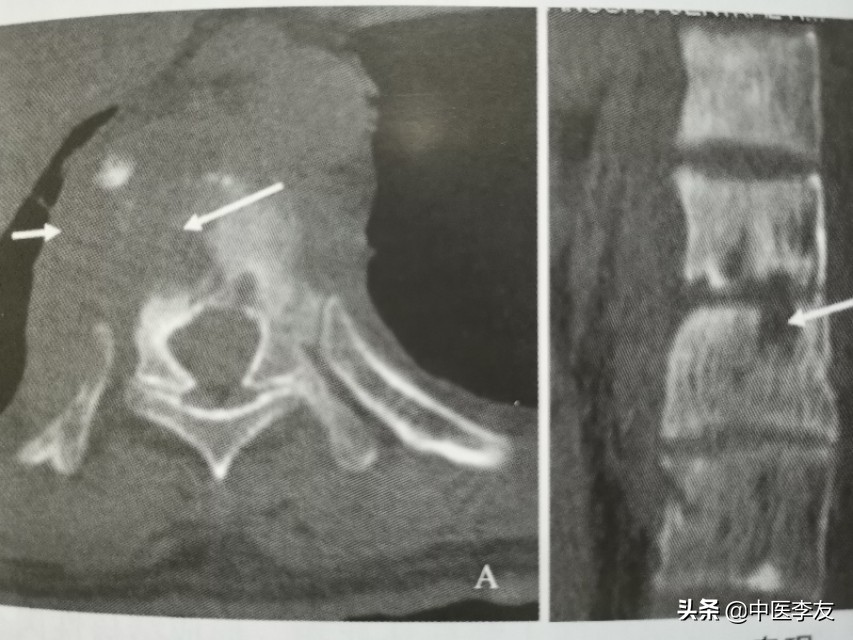

2.CT,表现与X线表现类似,但是有它自己特点:①能更清晰地显示骨质破坏,特别是较隐蔽和较小的破坏;②更容易发现死骨及病理骨折碎片;③增强扫描冷脓肿周边强化,内部无强化,可更好地了解冷脓肿的位置、大小,与周围大血管、组织器官的关系;④显示脓肿或骨碎片突入椎管内的情况

3.MRI,表现是显示脊椎结核病灶和范围最敏感的方法,可发现椎体内早期炎性水肿。病灶T1WI表现为低信号,T2WI多表现为混杂高信号;GD-DTPA增强不均匀强化。脓肿和肉芽肿在T1WI上呈低信号,T2WI多为混杂高信号,部分均匀高信号,增强检查肉芽肿不均匀,均匀强化,脓肿壁薄且均匀的环状强化。